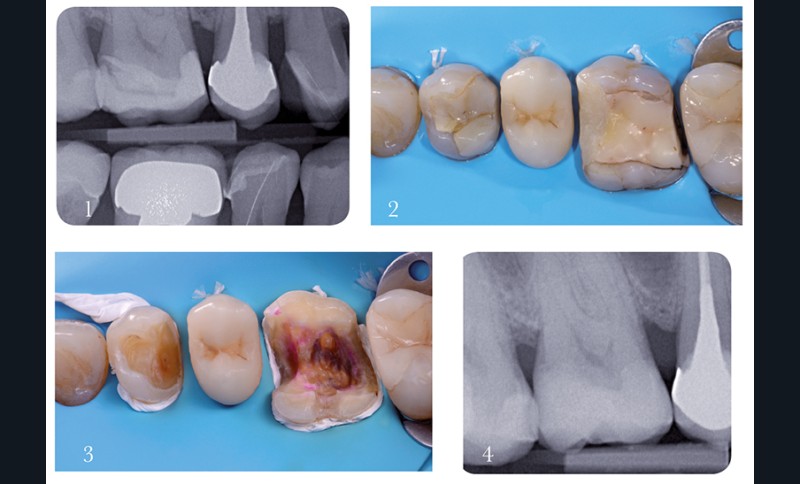

Cas 1 – digue et excavation des tissus cariés

1. 14 et 16 sont à traiter.

2 . Afin de faciliter le franchissement des zones de contact proximales, les contours irréguliers et tranchants

des anciennes obturations sont préalablement éliminés. La zone cervicale n’est pas concernée par cette préparation initiale ; elle doit guider le latex en profondeur dans le sulcus. Afin d’obtenir d’emblée la meilleure rétraction gingivale possible, des doubles ligatures sont mises en place sur 14 et 16.

3 . Dans les zones les plus sous-gingivales (concavité mésiale de 16 en particulier), un surplus de rétraction

est nécessaire. La mise en place d’une bande de téflon additionnelle offre une rétraction verticale et horizontale qui permet de nettoyer les tissus cariés sans risque d’endommager la digue.

4. La radiographie post-traitement confirme l’efficacité de l’excavation carieuse et l’ajustage satisfaisant de l’onlay en céramique.